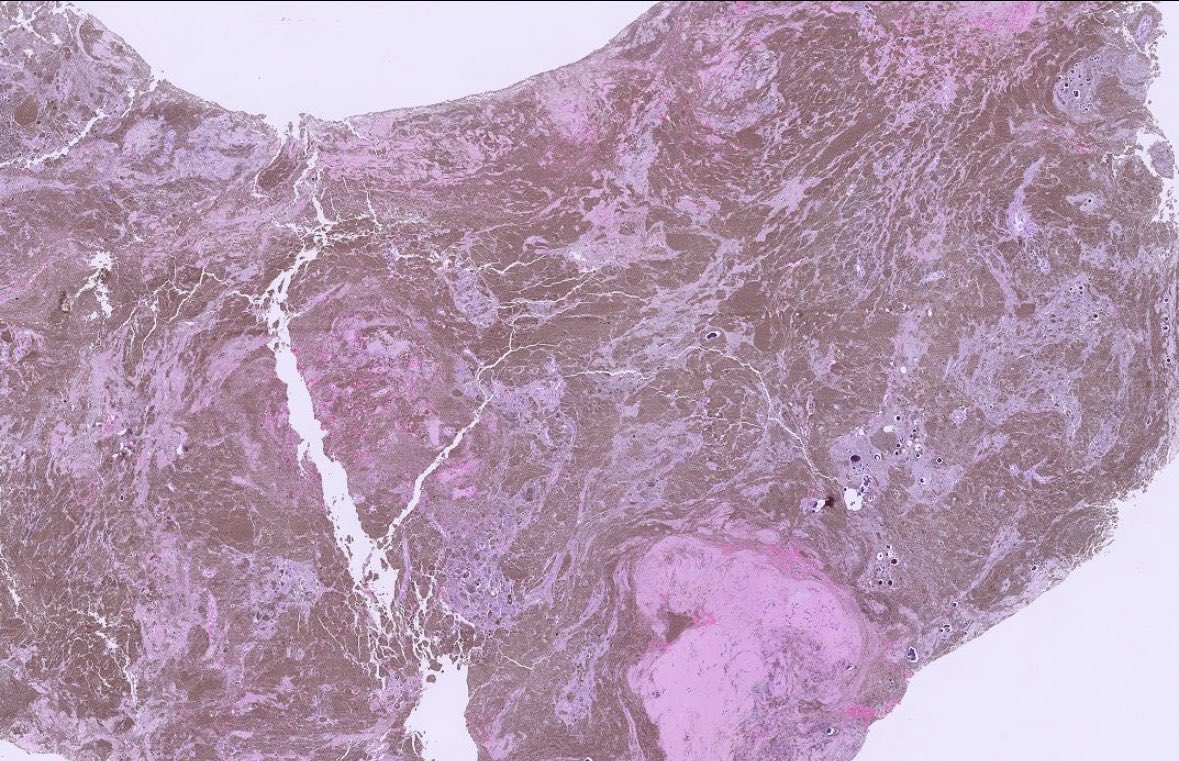

Adult Male. Dura based lesion. #PathX #PathTwitter #PathClassic #BSTPath #NeuroPath